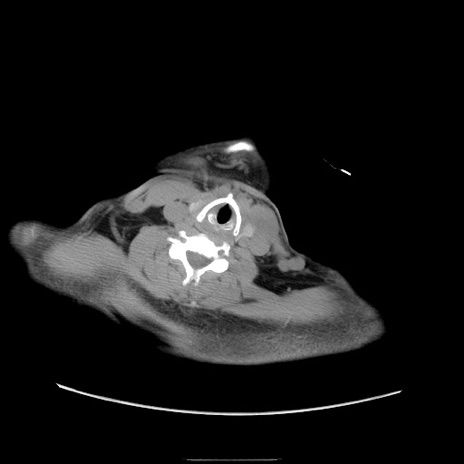

症例22(横断像)

【症例】50歳代男性

【主訴】腹痛

【現病歴】AVMからの被殻出血のため回復期リハ病棟入院中。 本日午後3時頃急に下腹部痛が出現した。

【既往歴】AVM、被殻出血、虫垂炎、高血圧

【身体所見】意識晴明、左半身不全麻痺、会話の理解は良好、36.5°C、腹部:膨隆、全体に板状硬、下腹部正中に圧痛点あり、反跳痛-、筋性防御不明、右下腹部にope scar

【データ】WBC 9400、CRP 0.06